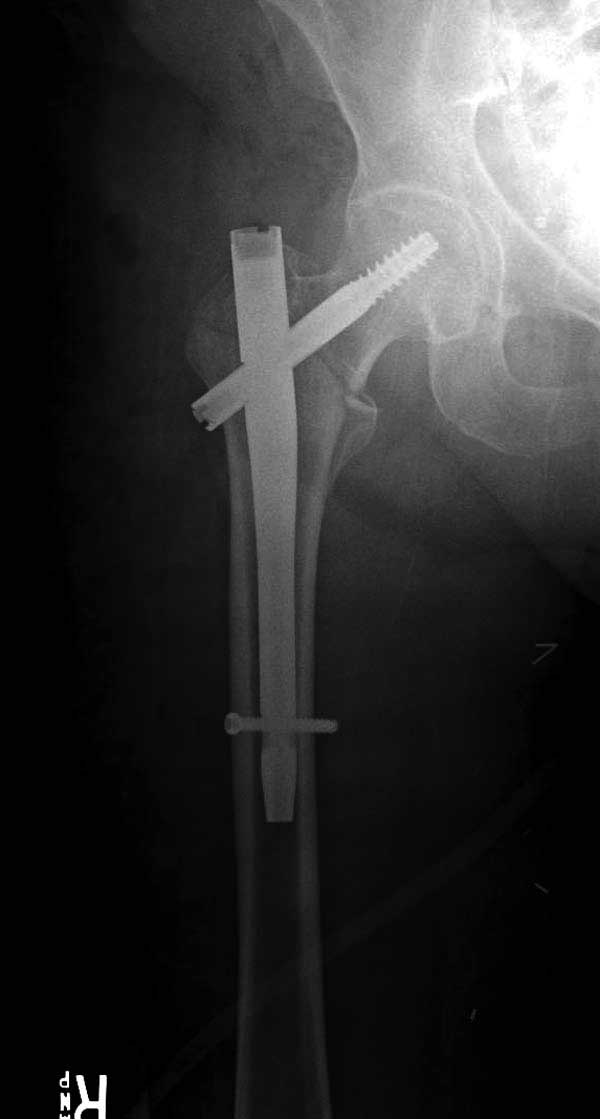

Первые снимки показывают технические погрешности установки DHS. Не была достигнута репозиция, конечность в флексии и шейка в ротации. Сегодня все меньше обращают внимание на параметры для оценки репозиции (S контуры Lowell в обеих проекциях и Garden Alignment Index, в норме 155 и 180 градусов), хотя такие простые тесты помогли бы дорепонировать смещение. Винт находится сзади в головке, что при нагрузке поменяет вектор и вместо компрессии в линии перелома срежет головку-Cut Out!

В зависимости от дистанции линии перелома и латерального кортекса надо использовать разной длины barrel, т.е. конец баррели не должен доходить до пределов перелома. Здесь конец длинного ствола упирается в медиальный фрагмент, что мешает созданию компрессии, а более короткий barrel создал бы запас для компрессии. В боковой пластине вместо 4х можно было ограничится двумя шурупами, потому что головка шурупа в 4.5 мм выдерживает давление до 350 кг.